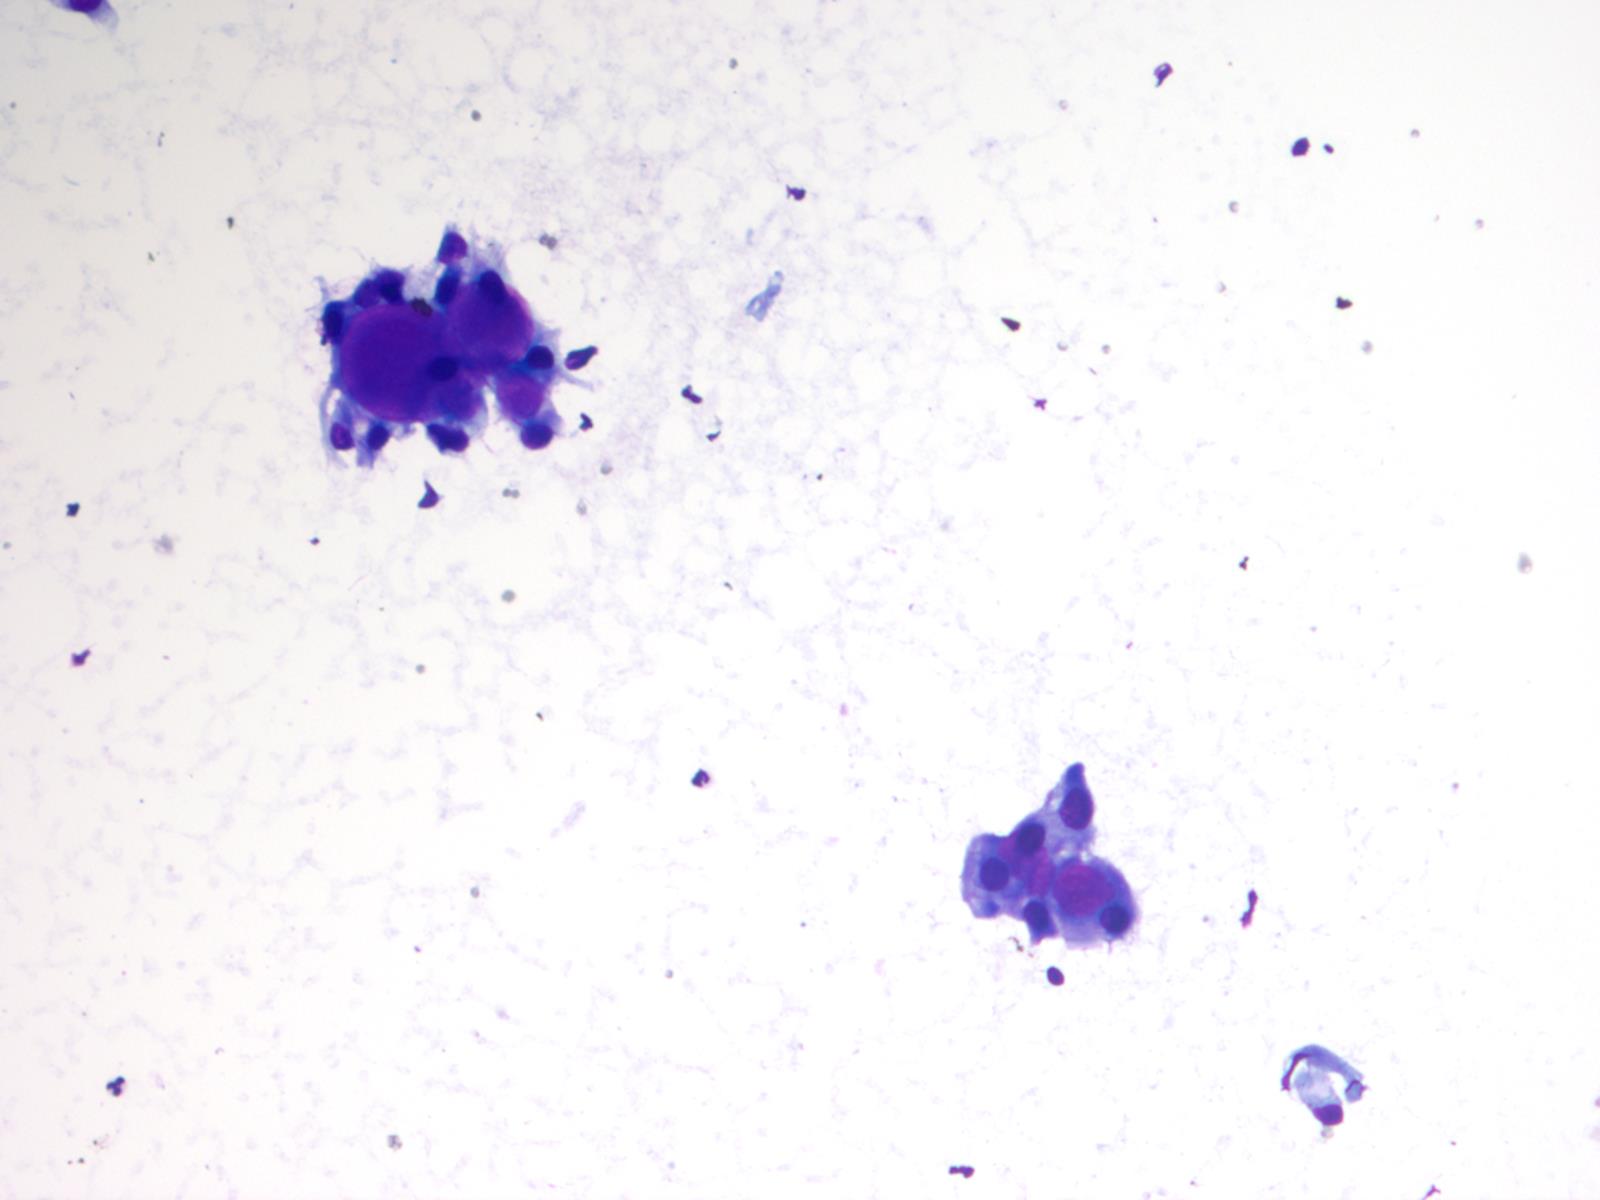

Frozen section description

- Intraoperative squash / smear preparation and frozen section reveals epithelioid to spindled tumor cells arranged around microcysts and forming papillary structures with perivascular myxoid change; these features are diagnostic in the appropriate clinical setting

Cytology description

- Cytology usually recapitulates the histologic findings; myxoid matrix and cells show nuclear uniformity and process formation

- Epithelioid to spindle cells

- Arrangement of tumor cells around blood vessels forms papillary structures with perivascular myxoid change

- Tumor cells are arranged around myxoid microcysts

Cytology images